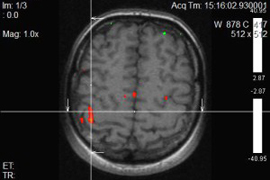

Նկարներում պատկերված է ձախ ձեռքի շարժիչ կենտրոնը, այն գտնվում է աջ կիսագնդի առաջկենտրոնական գալարում:

Ֆունկցիոնալ ՄՌՏ գնահատում է ուղեղի նեյրոնալ ակտիվության հետևանքով առաջացած հեմոդինամիկ փոփոխությունները, որի շնորհիվ հնարավոր է դառնում մեծ ճշգրտությամբ առանձնացնել ուղեղի կենտրոնները (խոսքի, տեսողության, շարժիչ և այլն): Չխորանալով մեթոդի ֆիզիկական սկզբունքների մեջ նշենք, որ ֆՄՌՏ-ի շնորհիվ կարելի է խուսափել կամ գոնե կանխատեսել հետվիրահատական նյարդաբանական դեֆիցիտները: Նախկինում նույնիսկ ամենաշնորհալի նյարդավիրաբույժները չէին կարողանում պատասխանել հիվանդների հարցերին, կապված հետվիրահատական բարդությունների հետ: Դա առաջին հերթին պայմանավորված է անատոմիական յուրահատկություններով, հարկ է նշել, որ պացիենտների գլխուղեղի ֆունկցիոնալ զոնաները լրջորեն կարող են տարբերվել բժշկական համալսարաններում օգտագործվող անատոմիական ատլասներում ներկայացված գլխուղեղի զոնաներից: Հետևաբար վիրաբույժի աչքի համար անտեսանելի կենտրոնները շատ հաճախ վնասվում էին և վիրահատությունից հետո պացիենտները դժվարանում էին ինքնուրույն տեղաշարժվել, կորցնում էին ինքնասպասարկման տարրական ունակությունները, խոսքի կարողությունը: